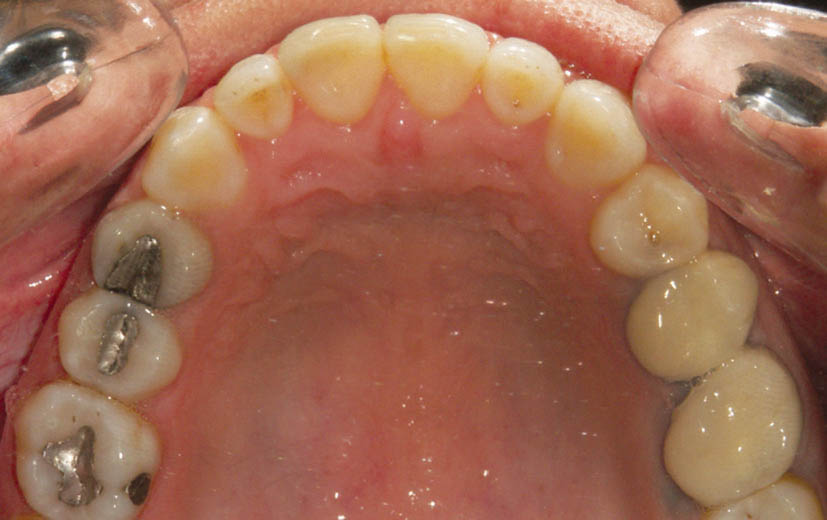

در بُعد افقی ناحیه کانین شما Laceback را دارید. وقتی کانین در ابتدای درمان Tip صحیح ندارد، اولین آرچ وایر (0.012 سوپرالاستیک یا 0.016 حرارتی) یک انحنایی بر میدارد تا درون شیار براکت قرار بگیرد (شکل 13-3).

شکل 13-3: کانین راست بالا با تمایل دیستاله تاج؛ سیم باید خمی بردارد تا درون شیاربراکت قرار گیرد.

آرچ وایر بخاطر خاصیت فنری خود به مرور زمان صاف میشود، لذا دندان کانین بعد از مدتی به Tip خود میرسد (تاج کانین مزیاله و ریشه دیستاله میشود). حرکت مزیالی تاج بیشتر از حرکت دیستالی ریشه است (شکل 14-3)، لذا تاج پروترود و در قوس بزرگتری قرار میگیرد.